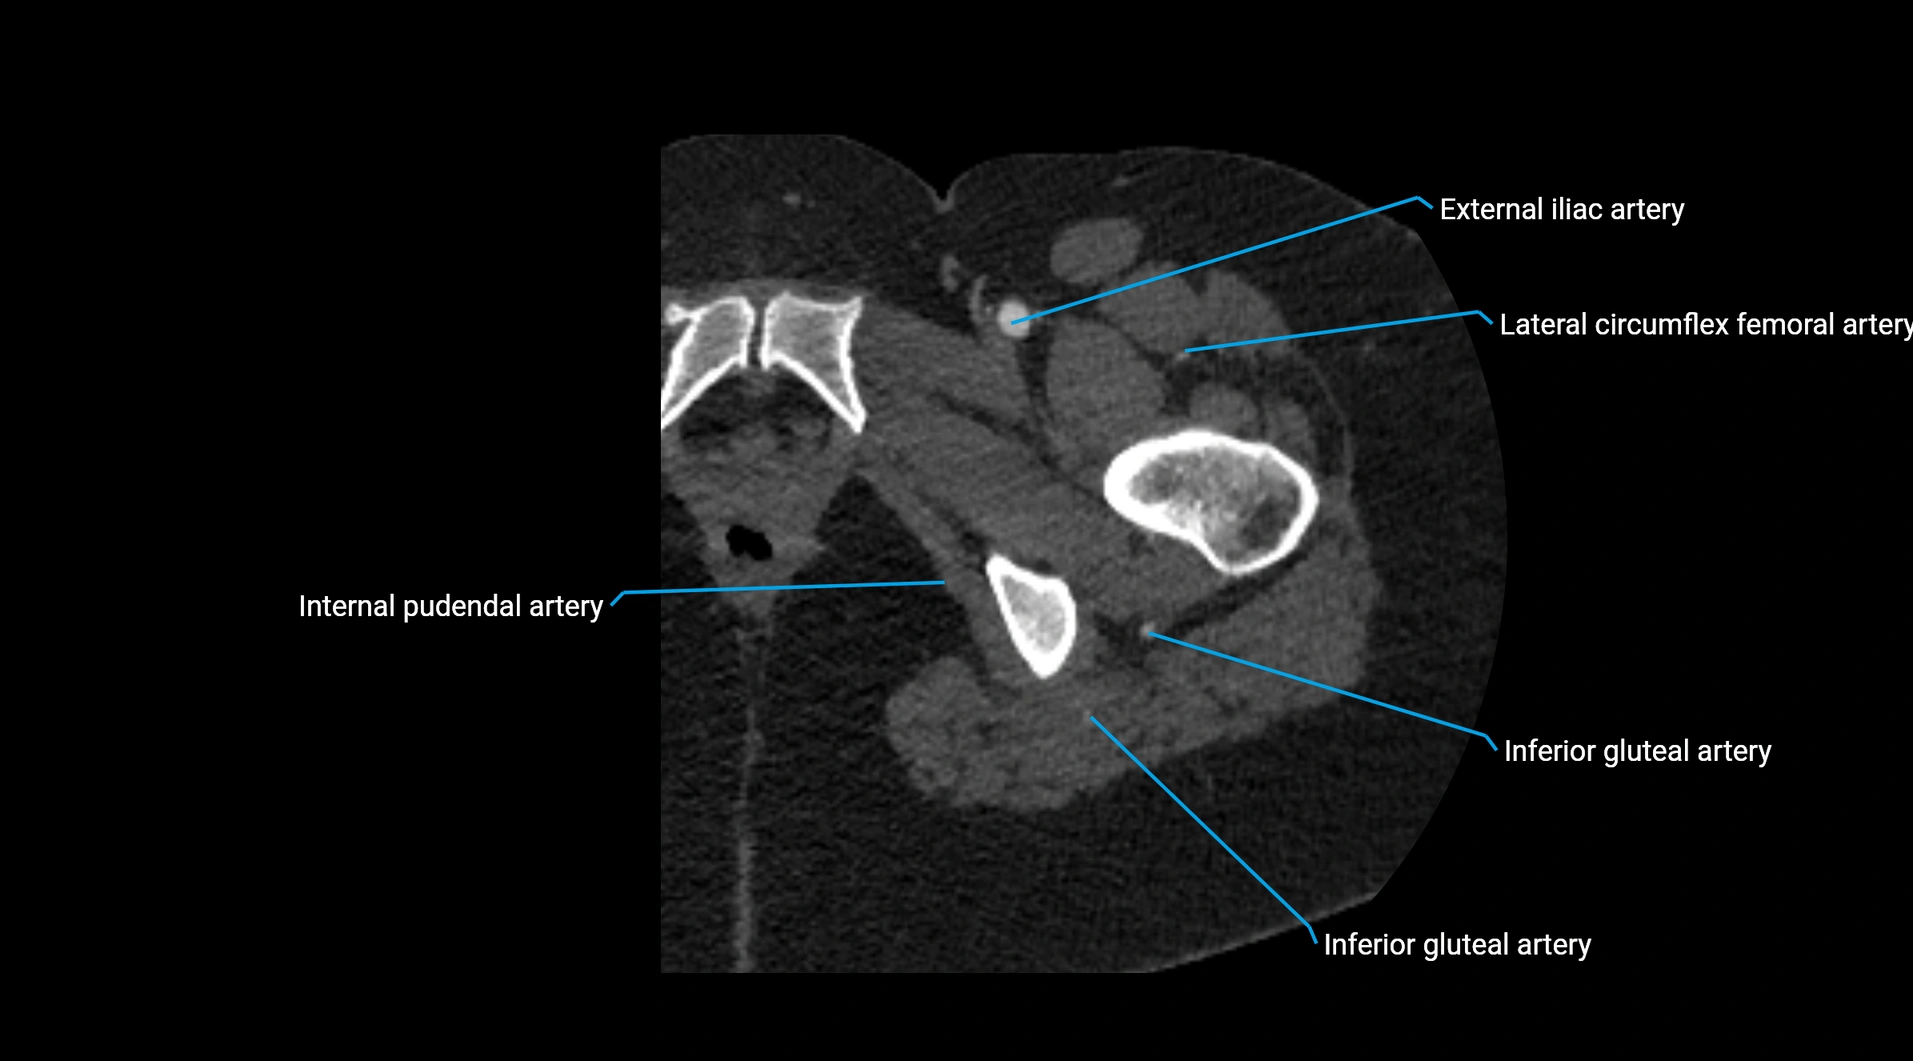

Contrast-enhanced CT (CTA):

• Gold standard for abdominal aortic imaging

• Provides excellent detail of lumen, wall, aneurysm, thrombus, and branch vessels

• Multiplanar and 3D reconstructions help in aneurysm measurement, stent graft planning, and dissection evaluation